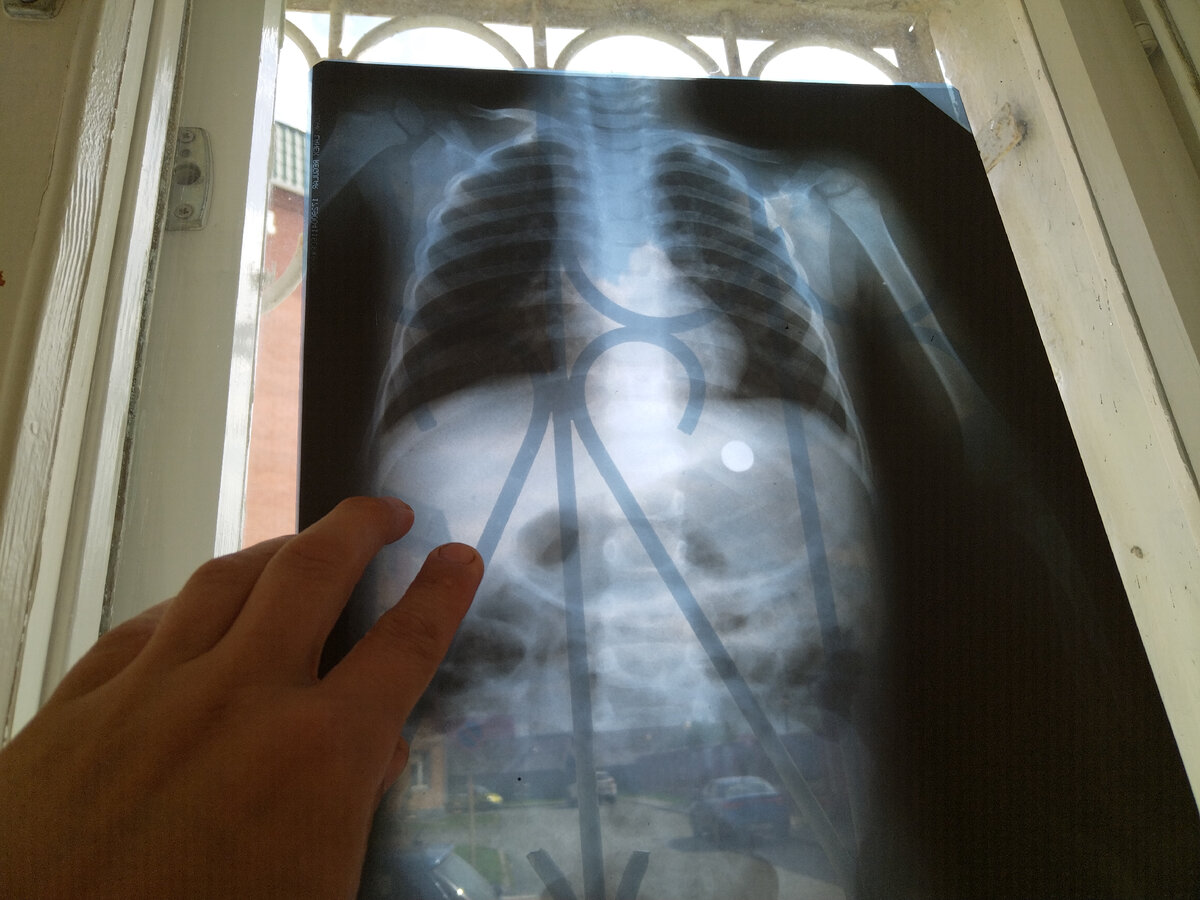

Итак, клинический случай. Ребёнок 2 года проглотил батарейку. Несмотря на, казалось бы, безобидные слова, надо понимать, что случай предельно серьёзный. Батарейку надо доставать быстро, пока она в желудке, и до нее можно дотянуться эндоскопом. Если этого не сделать, то в лучшем случае, будет операция, а в худшем - перитонит, со всеми вытекающими.... В общем, начали мы (анестезиологи) по полной: полноценный наркоз с искусственной вентиляцией легких (никаких полумер - чтобы защитить дыхательные пути). А потом начались проблемы.

Надо сказать, что батарейка (таблетка) - это достаточно неудобный для эндоскопии объект. Имеющимися в арсенале нашей ЦРБ эндоскопическими средствами подцепить ее не удавалось. И тут включился мой бредогенератор в ход пошло мышление, работающее на стыке мастерской и операционной.